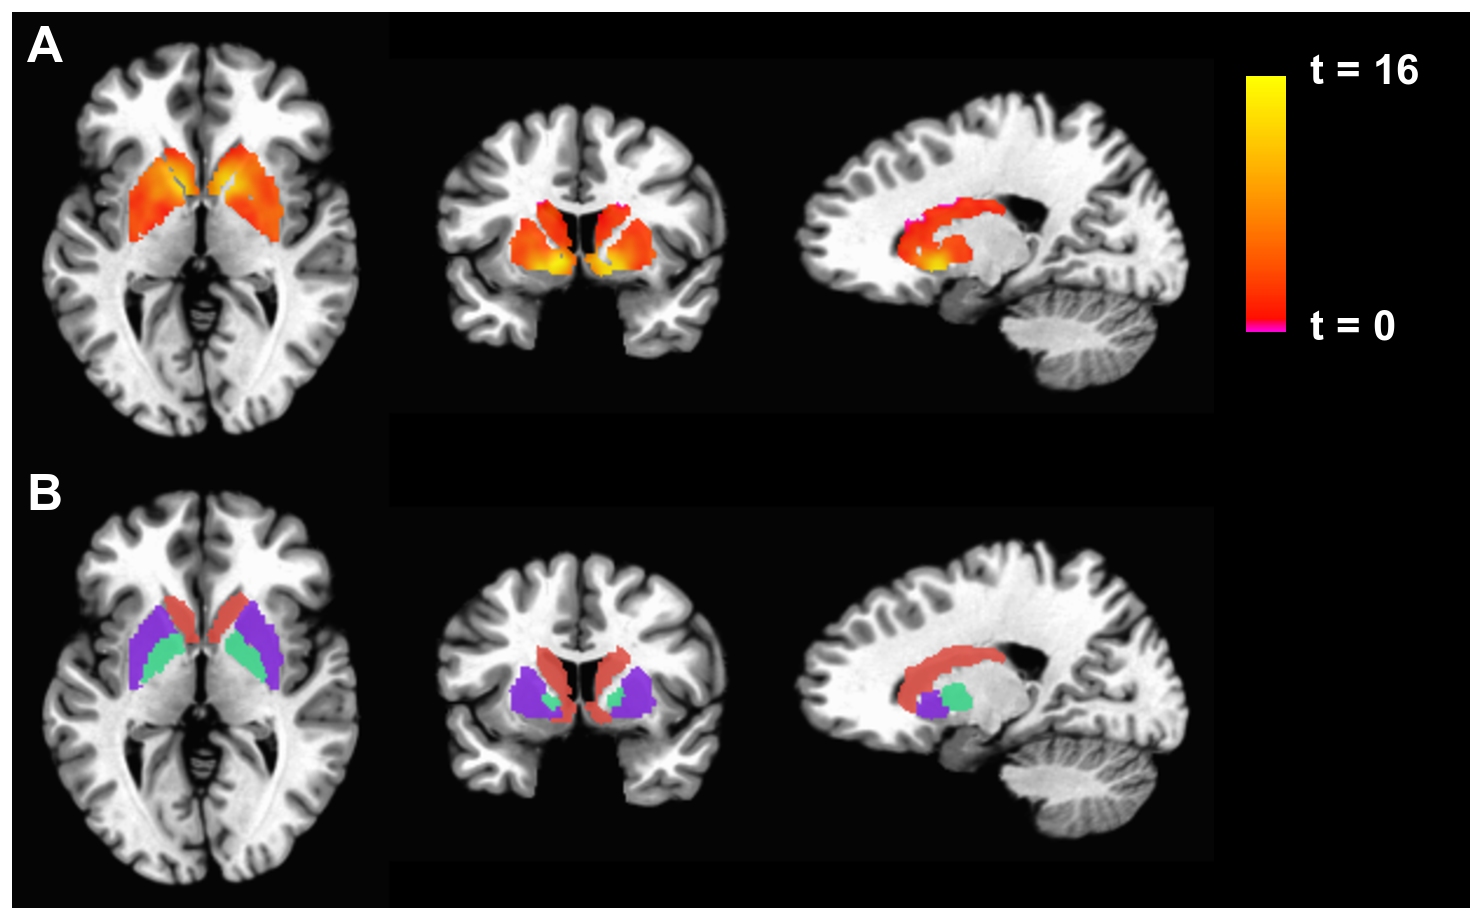

Functional MRI (fMRI) is a specialised type of MRI scan that measures brain activity by detecting changes in blood flow using the blood-oxygen-level-dependent (BOLD) contrast technique7,8. It enables the non-invasive observation of brain function and connectivity and is used to study brain function in various neurological and psychological applications. For example, fMRI has been employed to understand brain network connectivity in stroke patients, revealing differences in functional connectivity that can inform prognostic and rehabilitation strategies9.